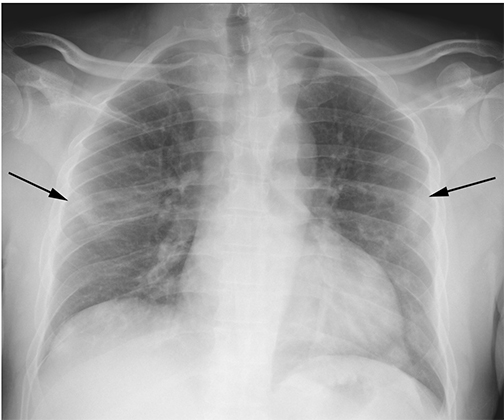

chest x-ray suggesting COVID

“In mid to late March of this year, when COVID-19 cases were spiking in New Orleans, we recognized an unusual pattern on chest x-rays that seemed to correlate with COVID positivity,” notes David Smith, MD, Associate Professor of Clinical Radiology at LSU Health New Orleans School of Medicine.

The radiologists conducted a retrospective study of nearly 400 persons under investigation (PUI) for COVID-19 in New Orleans. They reviewed the patients’ chest x-rays along with concurrent reverse-transcription polymerase chain reaction (RT-PCR) virus tests. Using well-documented COVID-19 imaging patterns, two experienced radiologists categorized each chest x-ray as characteristic, nonspecific, or negative in appearance for COVID-19.

The radiologists found a characteristic chest x-ray appearance is highly specific (96.6%) and has a high positive predictive value of 83.8% for SARS-CoV-2 infection in the setting of pandemic.

“The presence of patchy and/or confluent, band-like ground glass opacity or consolidation in a peripheral and mid-to-lower lung zone distribution on a chest radiograph is highly suggestive of SARS-CoV-2 infection and should be used in conjunction with clinical judgment to make a diagnosis,” says Bradley Spieler MD, Associate Professor of Diagnostic Radiology and Vice Chairman of Research in the Department of Radiology at LSU Health New Orleans School of Medicine.